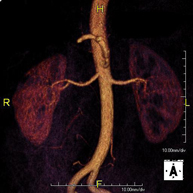

Prueba diagnóstica no invasiva que consiste en la obtención de imágenes de alta definición anatómica de todo el cuerpo mediante el empleo de un campo electromagnético y ondas de radio (con un emisor y un receptor). No utiliza radiación ionizante. Es una prueba muy importante en la búsqueda de metástasis en pacientes con neoplasia conocida. No requiere preparación previa. No es necesario el empleo de contraste paramagnético (Gadolinio). - Angio-RM Aorta abdominal

Prueba diagnóstica no invasiva que consiste en el estudio de la arteria aorta abdominal, obteniendo imágenes de alta definición anatómica mediante el empleo de un campo electromagnético y ondas de radio (con un emisor y un receptor). Es indispensable el uso de contraste paramagnético (Gadolinio). Sin embargo, no utiliza radiación ionizante. La calidad de las imágenes permite realizar reconstrucciones en 2D y 3D. Está indicado en aquellos pacientes con enfermedad vascular (aterosclerosis), estudio de aneurismas, en estudios pre-quirúrgicos de lesiones adyacentes a la aorta abdominal como "mapa" vascular, etc. - Angio RM Aorta-ilíaca

Prueba diagnóstica no invasiva que consiste en el estudio de la arteria aorta abdominal de las arterias ilíacas, obteniendo imágenes de alta definición anatómica mediante el empleo de un campo electromagnético y ondas de radio (con un emisor y un receptor). Es indispensable el uso de contraste paramagnético (Gadolinio). Sin embargo, no utiliza radiación ionizante. La calidad de las imágenes permite realizar reconstrucciones en 2D y 3D. Esta prueba está especialmente indicada como estudio pre-quirúrgico (mapa vascular) antes de intervenciones percutáneas o quirúrgicas de aorta abdominal y arterias ilíacas, estudio complementario en pacientes con isquemia de miembros inferiores, etc. - Angio RM Arterial extremidades inferiores